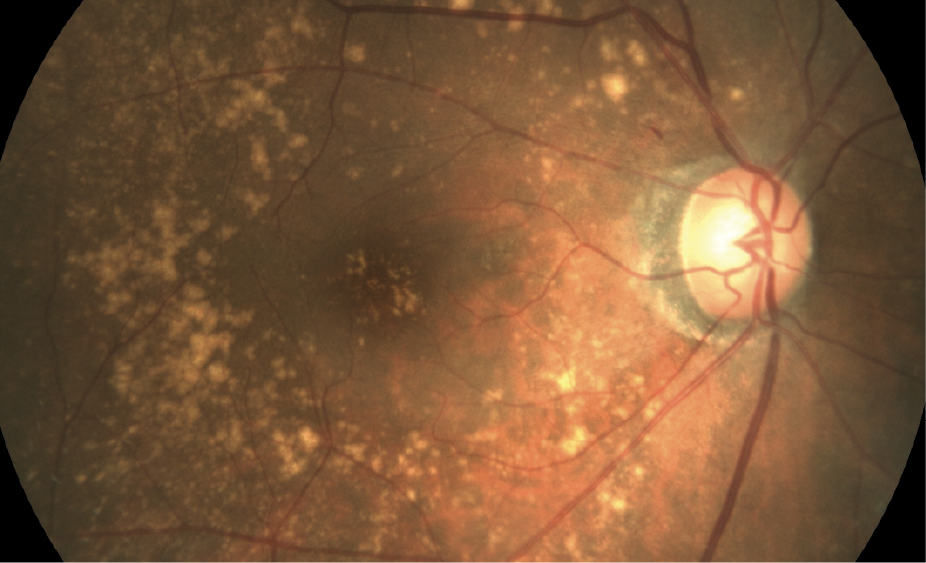

Approximately 85% to 90% of AMD cases are dry AMD, characterised in the early stages by proteinaceous deposits called drusen. This is asymptomatic initially, and is usually detected during screening, or when an individual presents with other ophthalmic issues. In the later stages of dry AMD, there is gradual thinning of the macula which result in central visual loss.

Yellow deposits (drusen) scattered throughout the retina. These deposits do not cause visual impairment.

Progressive thinning of the macula resulting in geographical atrophy and late stage central visual loss.